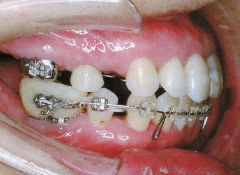

治療例1 (インプラント補綴+矯正)